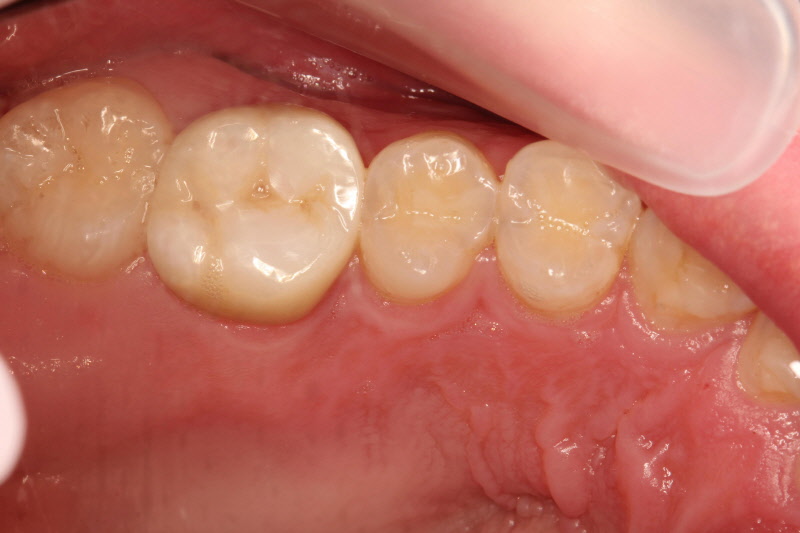

시간이 지난 후에도 좋은 상태를 유지하고 있는 아말감

이러한 장점은 있지만 수은에 대한 불안감과 안정성에 대한 논란이 항상 따라오게됩니다. 오랫동안 사용되면서 수은에 의한 직접적인 건강문제가 밝혀지지는 않았습니다. 굳고 나면 중금속에 해당하는 수은이 유리되어 나오지 않기에 안정성에는 큰 문제는 없는 것으로 보입니다.